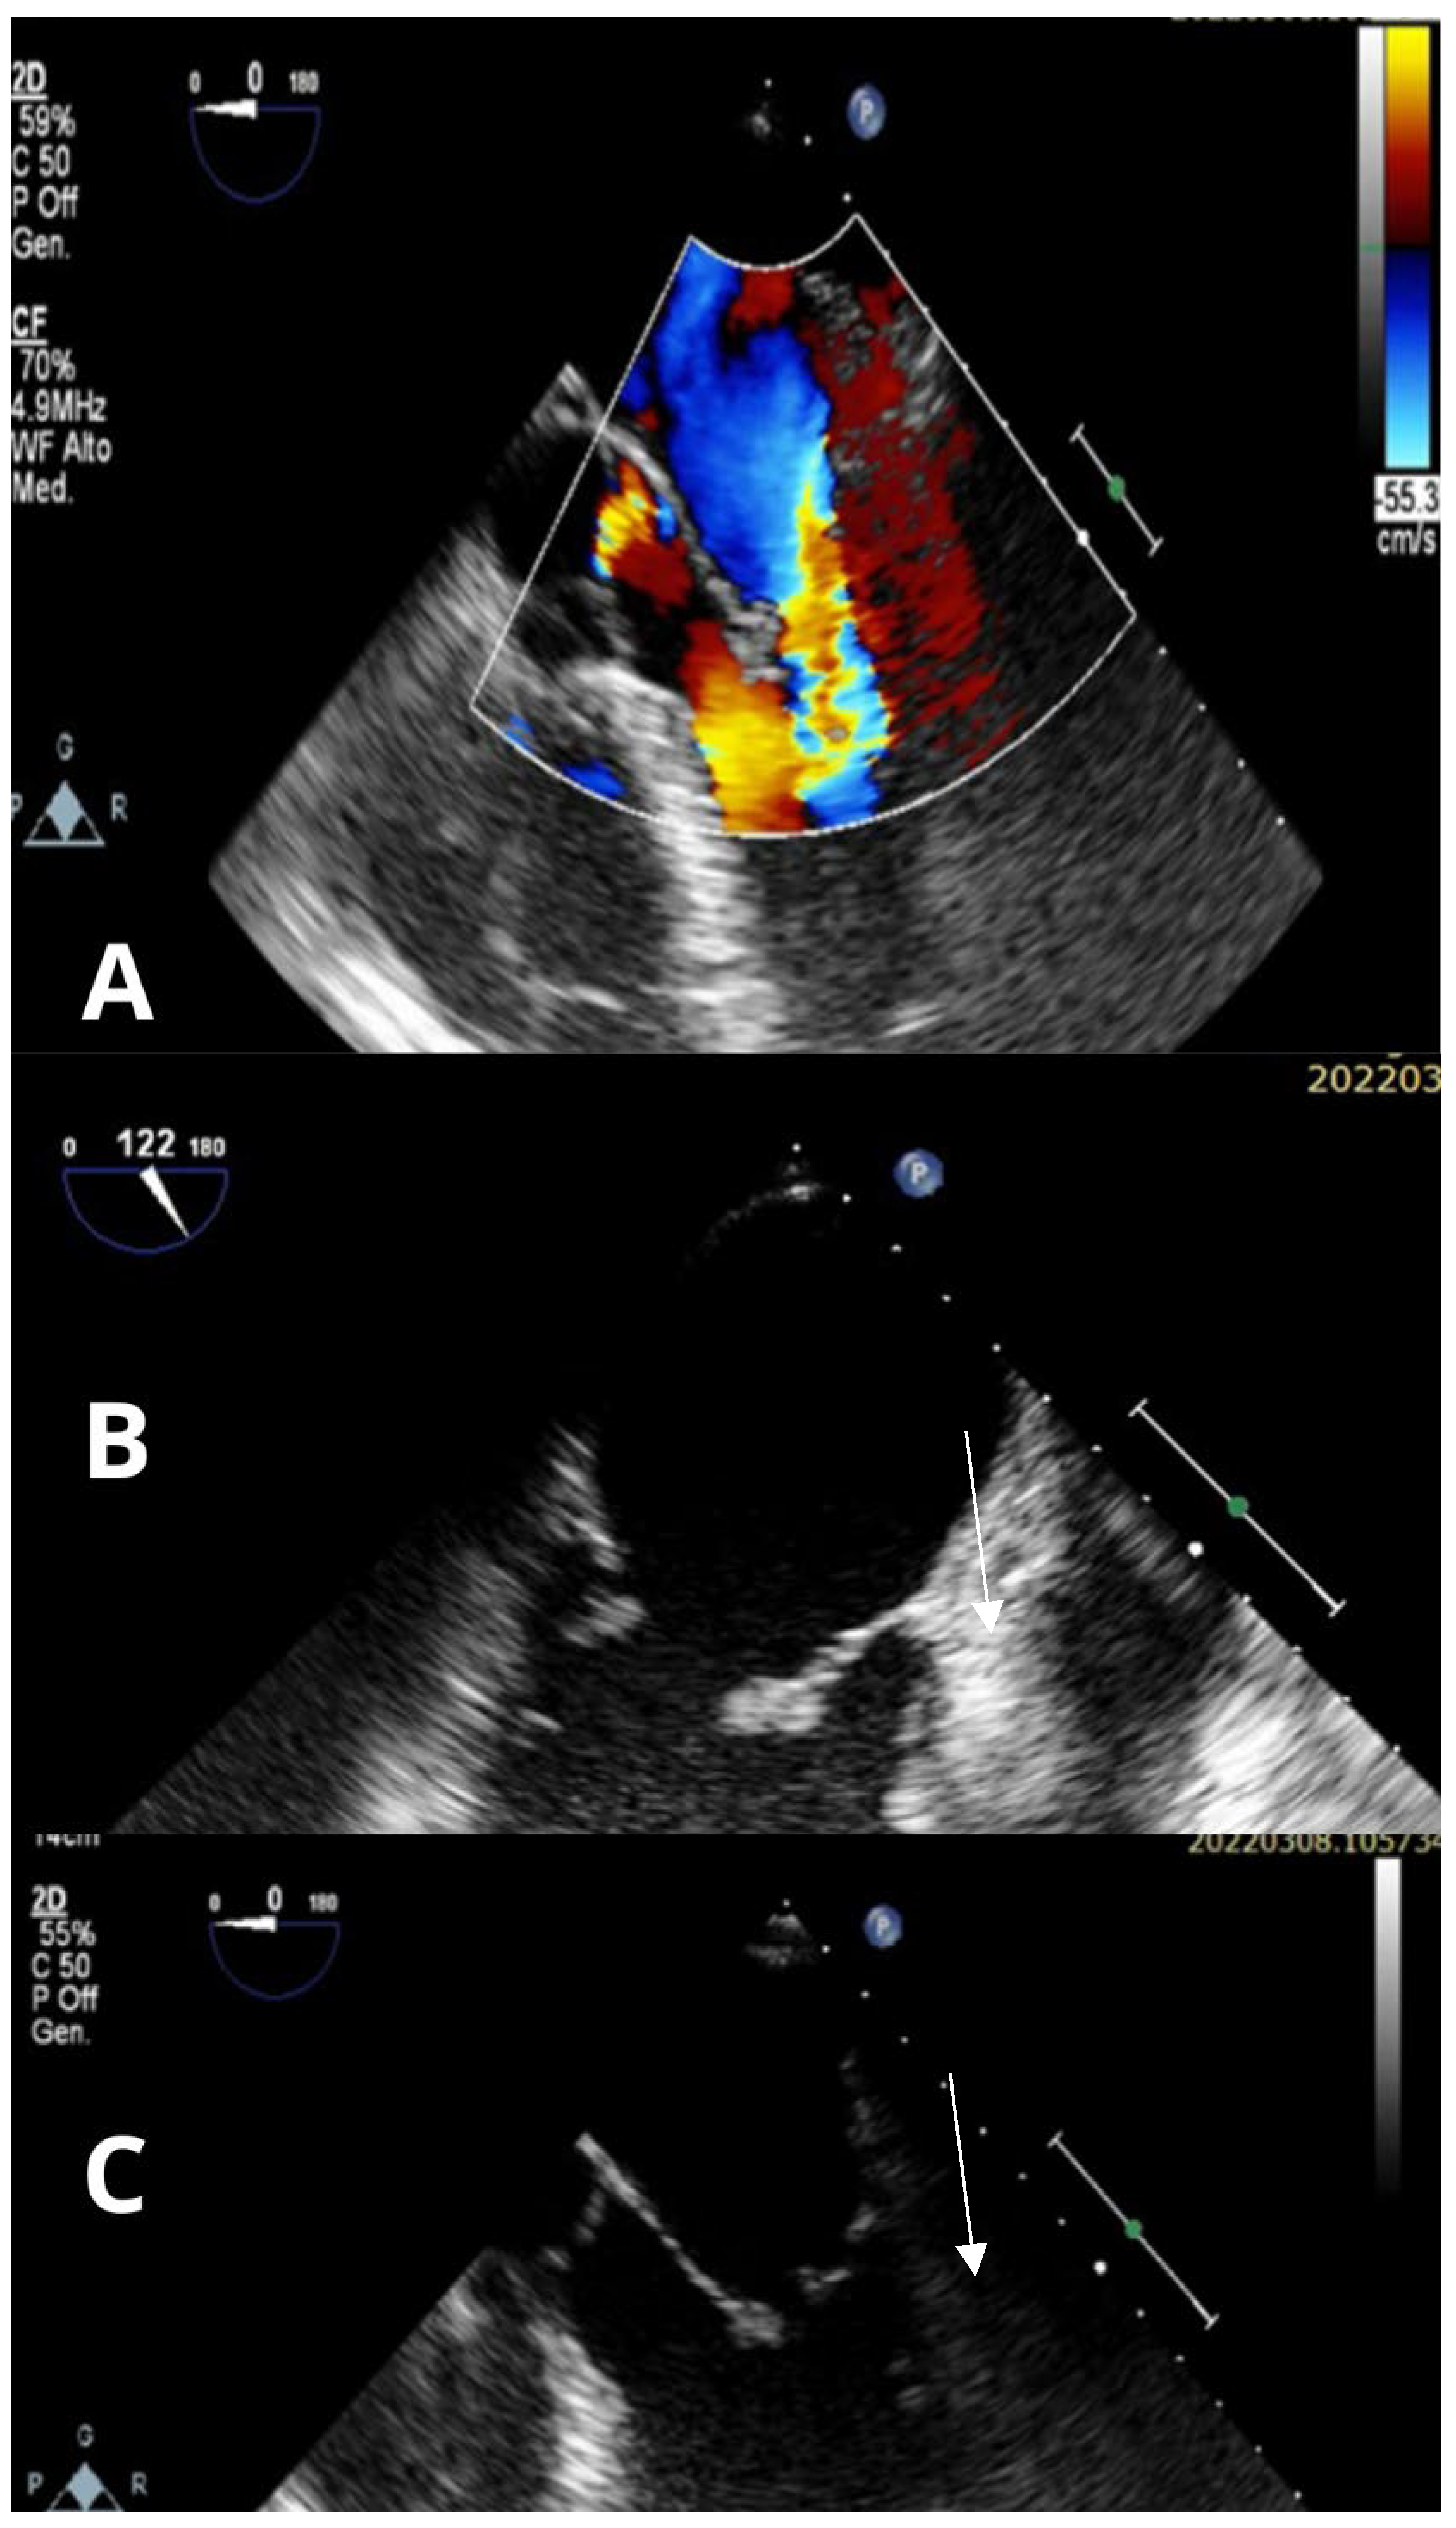

3. Case Report